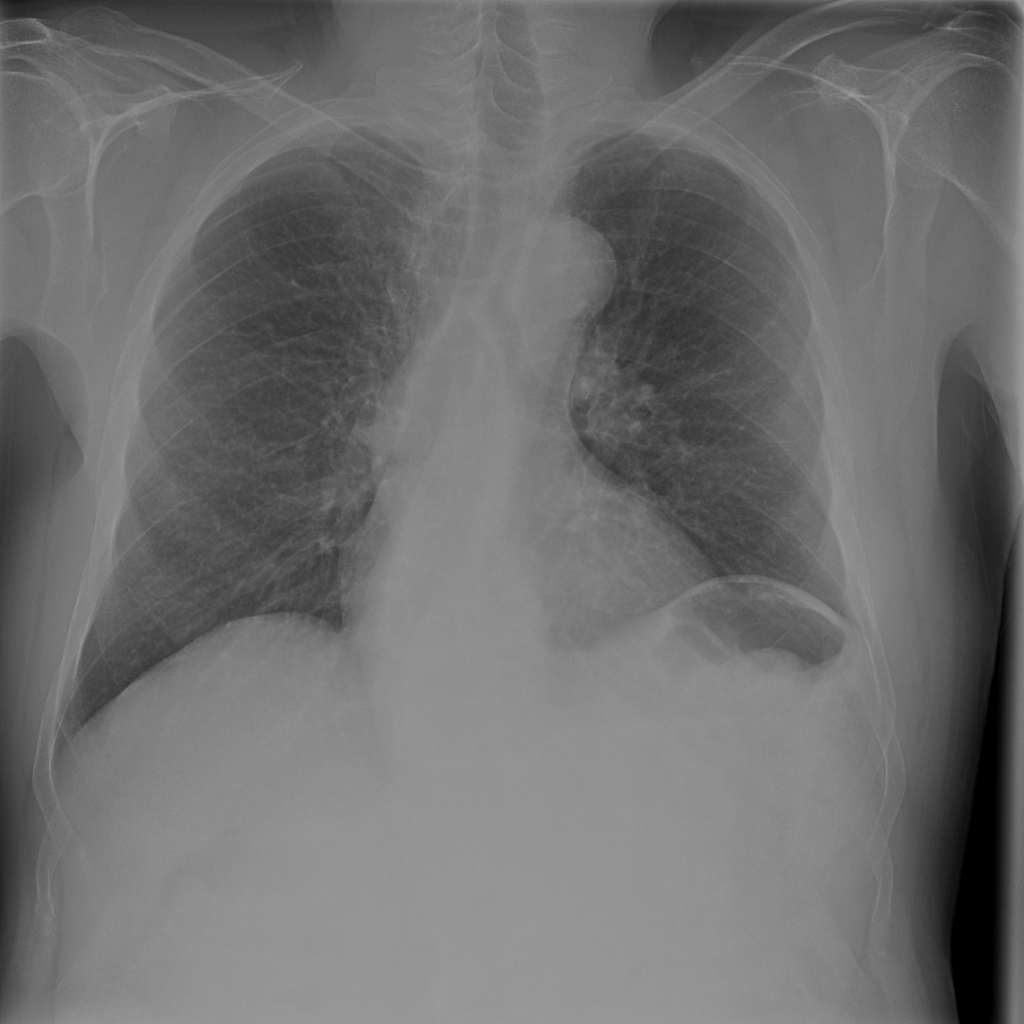

Showing up to 90 reference images for Hernia.

PAT-4F7E · IMG-000Hernia

PAT-4F7E · IMG-000

PA